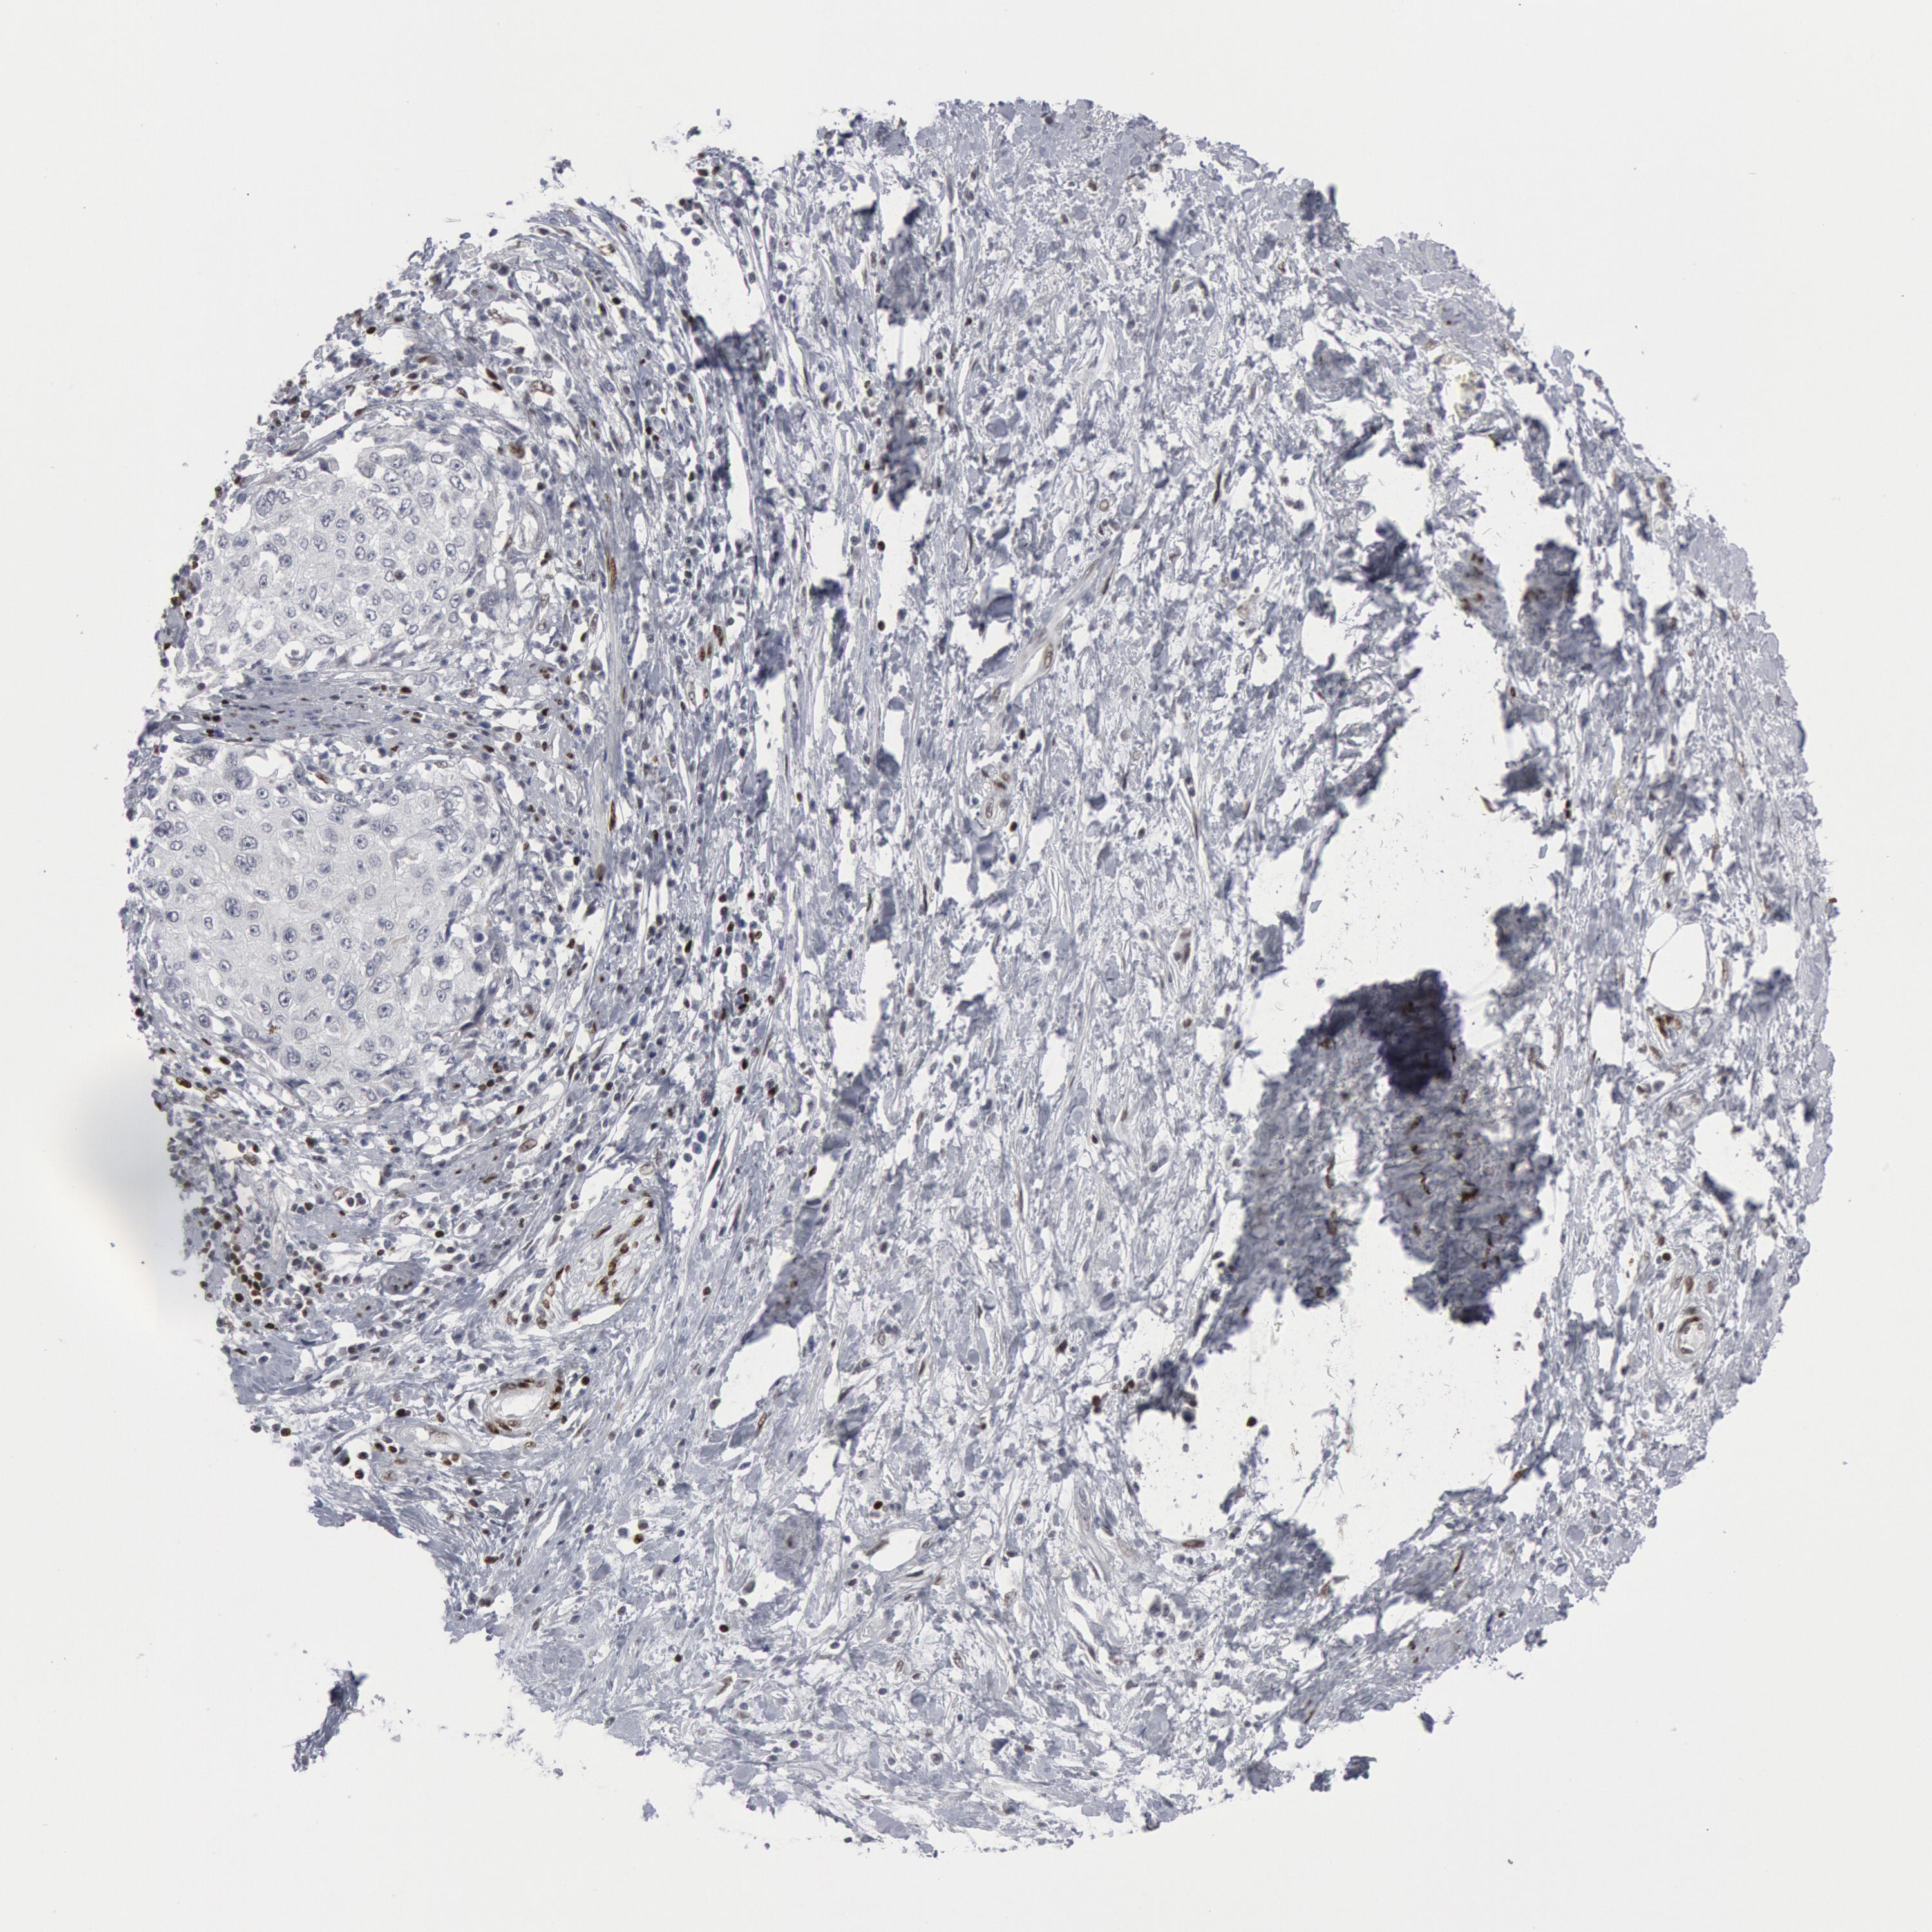

CERVICAL CANCER - Protein expressioni

A mouse-over function shows sample information and annotation data. Click on an image to view it in a full screen mode. Samples can be filtered based on level of antibody staining by selecting one or several of the following categories: high, medium, low and not detected. The assay and annotation is described here.

Note that samples used for immunohistochemistry by the Human Protein Atlas do not correspond to samples in the TCGA dataset.

Antibody stainingi

Antibody staining in the annotated cell types in the current human tissue is reported as not detected, low, medium, or high, based on conventional immunohistochemistry profiling in selected tissues. This score is based on the combination of the staining intensity and fraction of stained cells.

Each image is clickable and will lead to virtual microscopy that enables deeper exploration of all samples and also displays staining intensity scores, fraction scores and subcellular localization as well as patient and tissue information for each sample.

Antibody HPA000593

Antibody HPA001341

Antibody CAB037264

Staining

High

Medium

Low

Not detected

Intensity

Strong

Moderate

Weak

Negative

Quantity

>75%

75%-25%

<25%

None

Location

Nuclear

Cytoplasmic/membranous

Cytoplasmic/membranous,nuclear

Adenocarcinoma, NOS

Squamous cell carcinoma, NOS